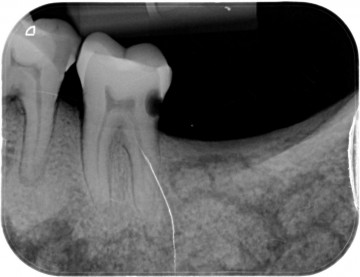

Zeer interessant ook  was dat  beiden   verstandskiezen ontbraken  en deze ook nooit ontwikkeld cq aangelegd waren .

(dit is een normaal verschijnsel) ,wat er dus op wijst dat  bij de ontwikkeling van het gebit dit bij de  vroeger mens ook al voorkwam .